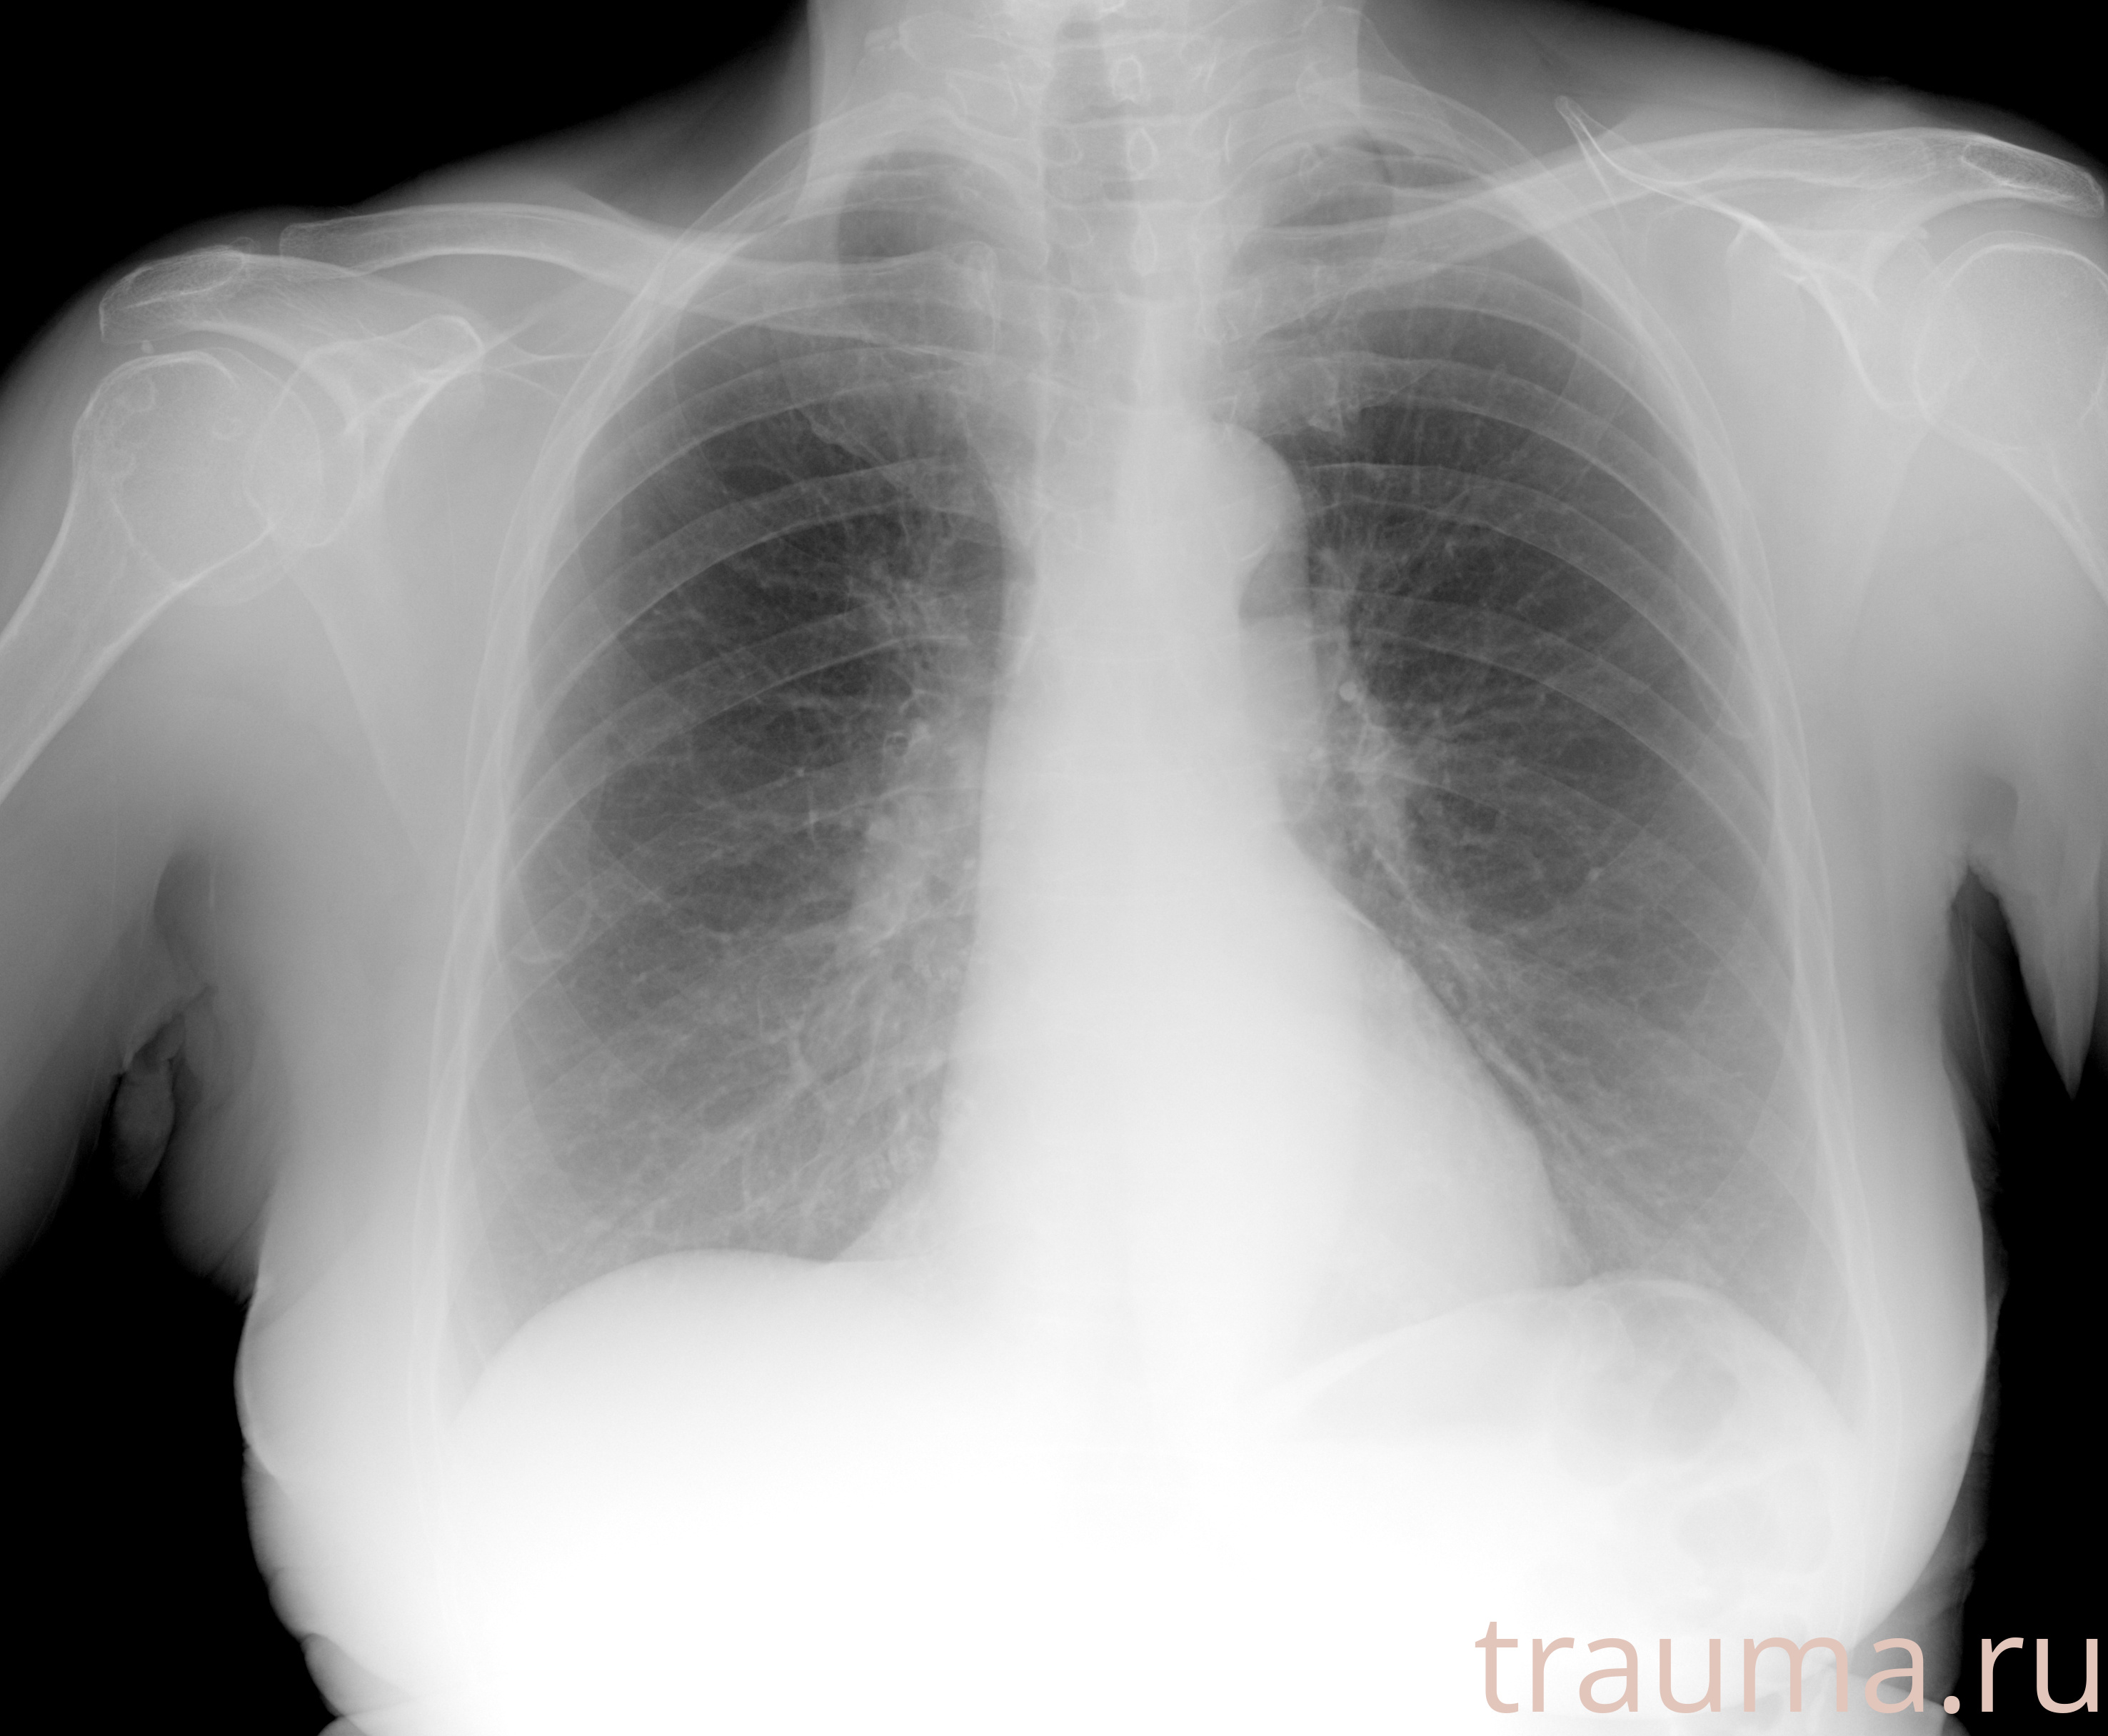

Рентген на дому: по вашему адресу приезжает врач-рентгенолог, травматолог-ортопед с мобильным рентгеновским аппаратом, проводит диагностику травмы или заболевания, делает необходимые рентгенограммы, дает рекомендации по дальнейшему лечению. Получить качественные снимки в домашних условиях возможно благодаря уникальной методике, разработанной МосРентген Центром для института  Склифосовского

при переломе шейки бедра и пневмонии от компании МосРентген Центр - партнера Института имени Склифосовского